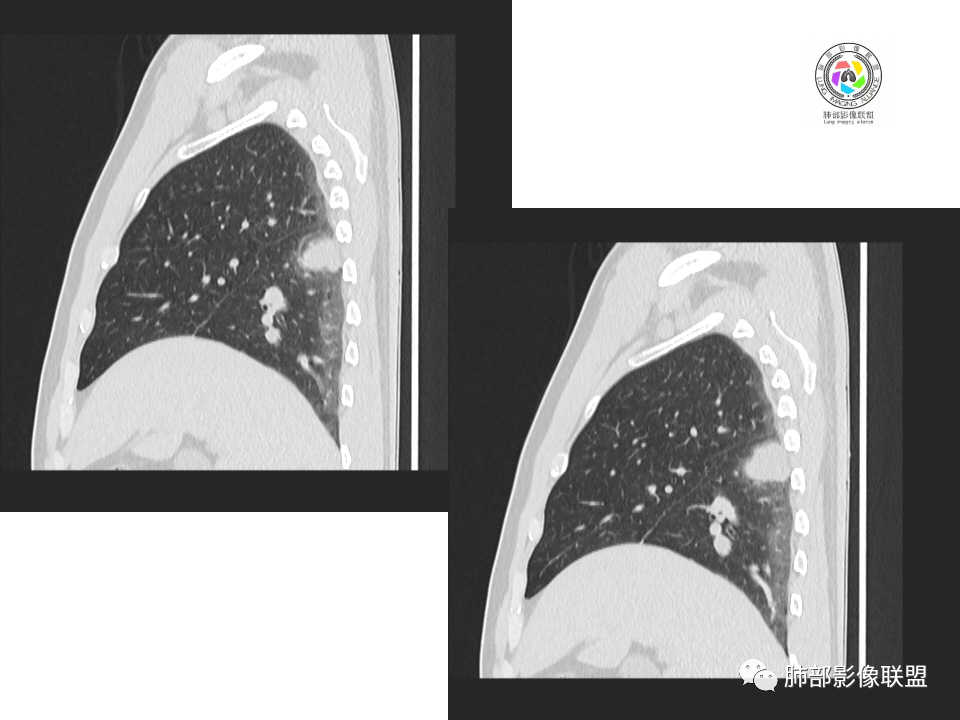

2.右肺下叶背段胸膜下块影,边界清楚光整,上下极见磨玻璃晕,未见明显分叶毛刺和棘状突起,未见胸膜凹陷或胸壁侵入。密度均匀,轻度不均匀强化。未见支气管进入。

4.右肺下叶基底段支气管血管束旁小结节影,边界清楚,强化不明显。注意,这结节在“遥远的”基底段。

中年男性,体检发现占位。右肺下叶背段胸膜下肿块,周围晕征,有小分叶,与支气管、肺内血管关系不清,形似山丘,重建可见肿块呈D字形凸向肺部。似跨斜裂,似有小凸起与肋下缘相连,增强似有轻微均匀强化。右肺下叶外基底段小结节,位于血管周围,部分边缘平直,轻微均匀强化。考虑二元:一、右下叶背段肿块为肺外病变,神经鞘瘤?SFT?鉴别小细胞癌、隐球菌病;二、右下叶外基底段结节考虑为良性结节、炎性肉芽肿?

3、卫星灶与“蘑菇兄弟”:诊断隐球菌时,建议找卫星灶,卫星灶可以在遥远的地方。可以是遥远地方的微小结节——“小蘑菇兄弟”。有些远处的卫星灶,通常是不规则饱满实性的,晕征不明显。隐球菌的卫星灶非常“隐”,但发现率高达60%多,诊断价值高。

4、卫星灶距离远的原因:隐球菌卫星灶常很远,推测:一次空气来源隐球菌感染进入双肺多处,部分定居繁殖;距离近的隐球菌“蘑菇兄弟”常常是二次感染。

5、周围毛刺纤维、边缘形态等:坏死包裹会使得结节变圆;结节多缺乏明显的分叶征,缺乏局部突出生长能力;如果出现分叶,是由多处肉芽肿中心形成。没有坏死的局限化,结节只是凑合在一起,常呈方形征;毛刺进入晕区(概念源自南边老师),毛刺较短、较软;周围的晕吸收后,会留下不规则边,外面常残留丝状条索;收缩力较弱,临近胸膜对胸膜牵拉不明显。